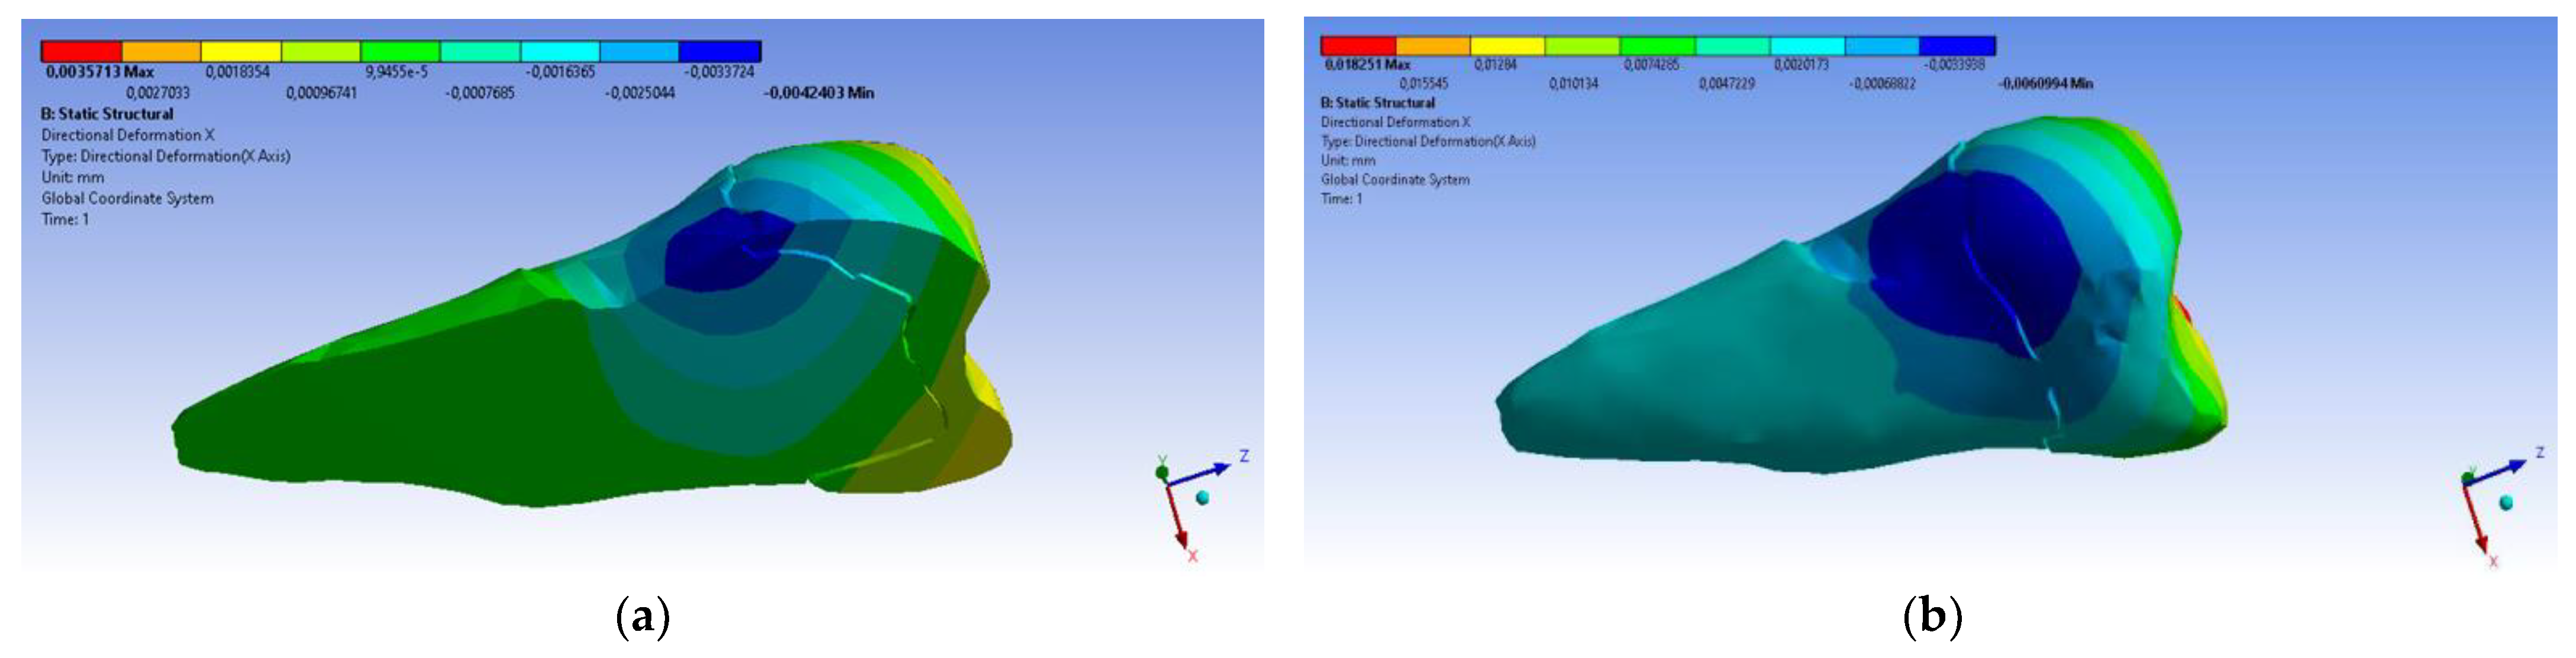

3. Finite Element Analysis (FEA) of Mandibular Right Premolars

| Minimum | 0 mm | −4.24 × 10−3 mm | −2.52 × 10−2 mm | −1.56 × 10−2 mm | 1.01 × 10−6 MPa | −35.6 MPa | −57.1 MPa | −104 MPa | −15.2 MPa | −152 MPa | −43.7 MPa | −39.6 MPa | −56.3 MPa |

| Maximum | 2.77 × 10−2 mm | 3.57 × 10−3 mm | 6.98 × 10−4 mm | 4.78 × 10−3 mm | 248 MPa | 61.5 MPa | 177 MPa | 72.2 MPa | 195 MPa | 21.4 MPa | 44.2 MPa | 117 MPa | 22.2 MPa |

| Minim. in | Cementum | Cementum | Enamel | Enamel | Cementum | Cementum | Enamel | Enamel | Enamel | Cementum | Enamel | Enamel | Cementum |

| Maxim. in | Enamel | Enamel | Cementum | Enamel | Cementum | Enamel | Enamel | Enamel | Enamel | Enamel | Cementum | Cementum | Cementum |